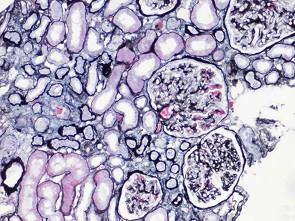

阅读下述三张狼疮性肾炎病理图片后,其病理诊断为 ( )A.Ⅲ型LNB.Ⅰ型LNC.Ⅳ型LND.微小病变病E.Ⅱ型LN

问题 阅读下述三张狼疮性肾炎病理图片后,其病理诊断为 ( )

选项 A.Ⅲ型LN B.Ⅰ型LN C.Ⅳ型LN D.微小病变病 E.Ⅱ型LN

答案 A